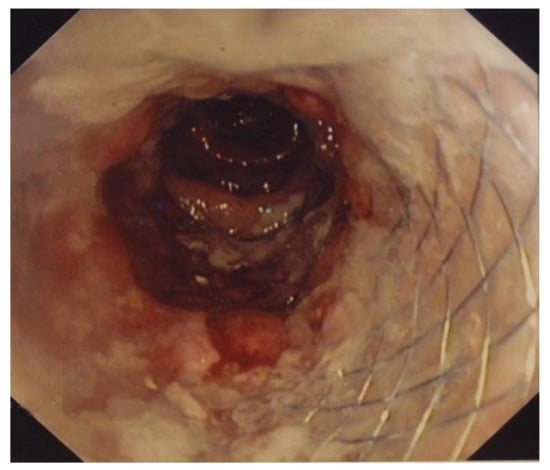

2.3. SEMS Placement